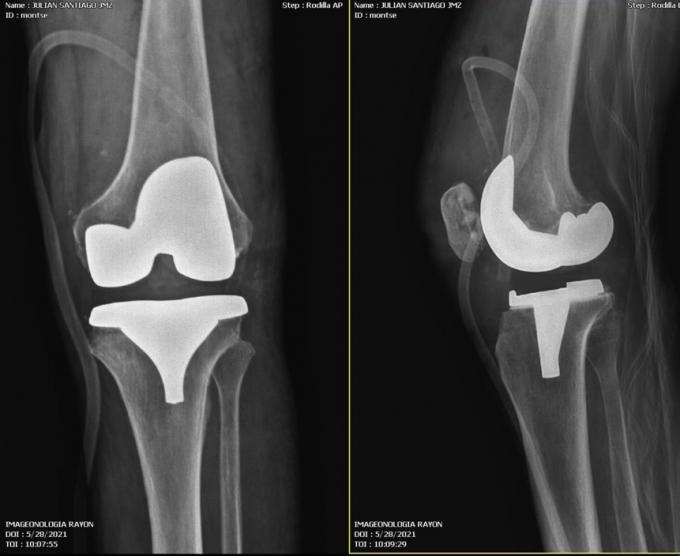

Sucess TKA Surgical in Latina America

Artificial Knee Joint Replacement Orthopedic Surgical

2021 , Latina America